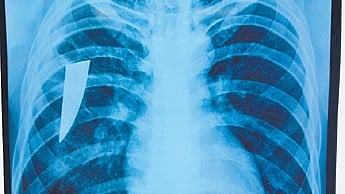

Twenty-two-year-old Santosh Das of Kabisuryanagar was admitted to the CTVS department on April 19 due to chest pain and blood in his cough. Subsequently, an X-ray detected a piece of a knife in his right side chest. On being questioned, Santosh said that while working in Bengaluru in 2022, he was stabbed on the left side of his neck by a local during a brawl. He was admitted to a hospital for treatment. However, the piece of knife was not detected and he returned to his native after recovery.

CT scan and bronchoscopy report showed the knife piece stuck in his chest and a surgery was conducted by head of the CTVS department Prof Sarada Dash. “The broken knife piece of 8 cm was retrieved from the right side lung and the patient is stable and undergoing treatment in ICU of CTVS department,” said Prof Dash.